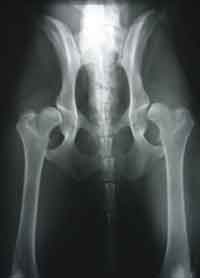

HD (Hüftgelenksdysplasie)

HD ist eine Fehlbildung der Hüftgelenke - das heißt Oberschenkelkopf und Gelenkpfanne passen nicht korrekt aufeinander. Diese Fehlbildung kann unterschiedlich ausgeprägt sein und tritt oft beidseitig auf.

Wir unterscheiden zwischen 5 verschiedenen Schweregraden der HD.

HD-frei - A

Das Gelenk ist absolut unauffällig und der Norbergwinkel beträgt 105 Grad oder mehr

HD-Verdacht/Grenzfall - B

Der Norbergwinkel beträgt 105 Grad oder mehr und die Gelenkpfanne und/oder der Schenkelkopf sind leicht ungleichmäßig oder aber Gelenkpfanne und/oder Schenkelkopf sind gleichmäßig, aber der Norbergwinkel beträgt weniger als 105 Grad

leichte HD -C

Norbergwinkel 100 Grad oder kleiner, ungleichmäßiger Oberschenkelkopf und Gelenkpfanne. Unter Umständen sind auch schon leichter arthrotischer Veränderungen zu bemerken.

mittlere HD - D

Norbergwinkel größer als 90 Grad und deutliche Ungleichmäßigkeiten von Oberschenkelkopf und Gelenkpfanne. Veränderungen des Pfannenrandes und/oder arthrotische Veränderungen sind zu erwarten oder schon vorhanden.

schwere HD - E

Norbergwinkel weniger ald 90 Grad, abgeflachter Pfannenrand, auffällige Veränderungen an Oberschenkelkopf und Gelenkpfanne. Deutliche arthrotische Veränderungen sind zu erwarten oder schon vorhanden.